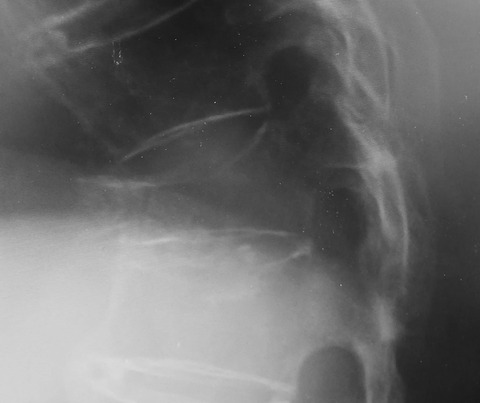

私たちは脊柱アライメントや椎体変形そのものに目が行きがちですが、それ以外にも各種の腹部症状を併発しうることを知っておくべきでしょう。

自治医科大学准教授の星地先生の経験・知識を余すところなく収めたサブテキストです。定番と言われている教科書に記載されている内容は素直に信じてしまいがちですが、実臨床との”ズレ”を感じることがときどきあります。このような臨床家として感じる、「一体何が重要なのか」「何がわかっていないのか」「ツボは何なのか」を自らの経験に基づいて完結に述べられています。